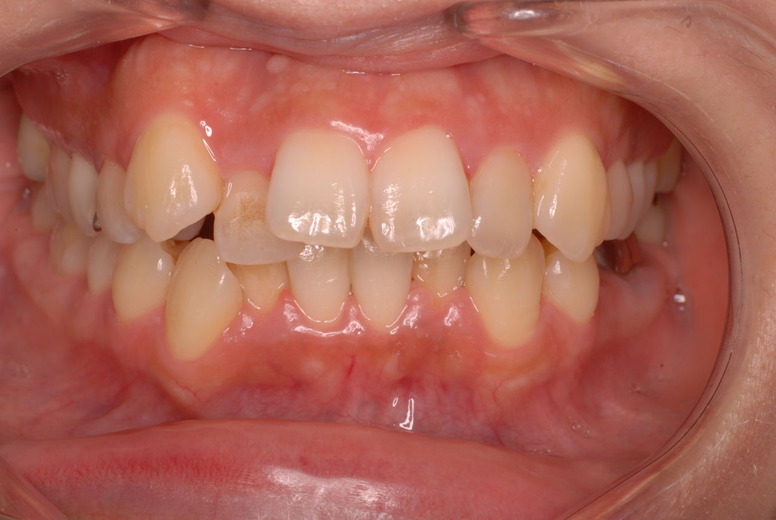

親知らずを取ることを嫌がる方が多いのですが、もし親知らずとその隣の14歳大臼歯の間に虫歯ができたり歯周病を罹患した場合、どれほど治療が大変で再発も起こりやすいか理解できない方がおおいのです。